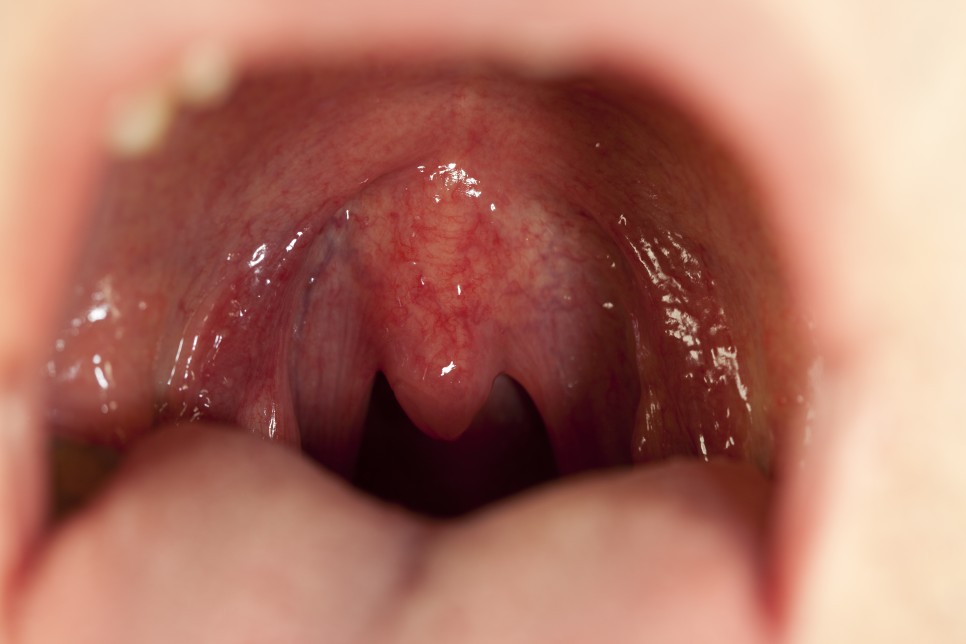

편

도결석은 편도 혹은 편도선에 있는 작은 구멍에 음식 찌꺼기나 세균 등이 뭉쳐서 생기는 쌀알 크기의 노란 알갱이를 말합니다. 다른 부위의 결석과 달리 딱딱하지 않아 합병증이나 문제를 일으키지는 않지만 심한 입냄새로 자신은 물론 상대방에게도 불쾌감을 주므로 신속히 제거 및 치료를 받는 것이 좋습니다.

편도결석 어떻게 생길까.편도결석의 주요 원인으로 만성 편도염을 들 수 있습니다.또한 양치질이 잘 되지 않는 등 편도위생상태가 불량한 경우에도 편도결석이 발생하기 쉽고 콧물이 목 뒤로 넘어간 후 비루가 있는 경우에도 편도에 이물질이나 세균이 번식하기 쉬워 편도결석이 생길 수 있습니다.